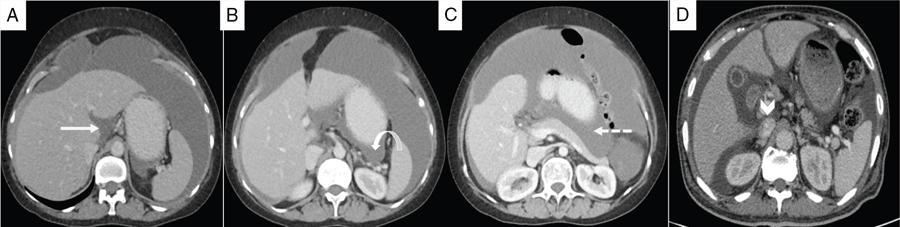

Shivsamb Jalkote, Slesha Bhalja, Disha Lokhandwala, Mansi Jantre, Karthik Ganesan Peritoneum is involved in a diverse group of primary as well as secondary pathologies ranging from the infective/inflammatory spectrum to malignancies. Peritoneal diseases are both common and potentially life threatening, and yet often get neglected in routine evaluation, due to the complex peritoneal anatomy and sometimes subtle imaging manifestations. The radiologist forms an integral part of the multidisciplinary team dealing with peritoneal pathologies and hence, having a lucid understanding of peritoneal anatomy, pathways of disease spread and different treatment options is paramount for an accurate radiological analysis. All three major serosal cavities (pleural, pericardial and peritoneal) of the body are derived from a single coelomic cavity, which is lined by a continuous mesothelium. At 2 weeks of gestational age, during the gastrulation stage, the embryo is a trilaminar disc, composed of the endoderm, mesoderm and ectoderm. During this stage, the development of the coelomic cavity commences as a consequence of morphological changes in the mesodermal cells leading to a coalition of the intercellular spaces. Peritoneum originates from mesoderm with its parietal layer developing from somatic mesoderm and visceral layer developing from splanchnic mesoderm. Initially, the peritoneum is an empty sac into which the growing gut tube protrudes (at 3 weeks of gestational age), resulting in the formation of the dorsal mesentery (formed by the fusion of two layers of the splanchnopleuric mesoderm) by which the gut tube is suspended lengthwise. The mesodermal cells opposed to the gut tube represent the future visceral peritoneum and those lining the body wall and the septum transversum form the future parietal peritoneum. Analogously, the ventral mesentery originates from the mesoderm of the septum transversum with the closure of the anterior abdominal wall, and, is short and not as extensive as the dorsal mesentery. The two mesenteries are aligned in the sagittal plane, subdividing the primitive peritoneum into right and left cavities, which are continuous anteriorly below the inferior edge of the ventral mesentery. With the development of various abdominal organs as buds from the gut tube, the capacity of the abdominal cavity diminishes, pushing the midgut loop into the umbilical cord. This physiologic herniation of the midgut takes place at the 6th week of gestation. Simultaneously, as the peritoneum drapes over the developing organs, there is compartmentalization of the cavity and a pattern of folds develops that eventually form the peritoneal ligaments. The majority of these ligaments arise from the ventral or dorsal mesentery. As the hepatic bud develops within the ventral mesentery, derivatives of the ventral mesentery can be divided based on their relation to the liver. The gastrohepatic ligament (lesser omentum) develops dorsally and the falciform, coronary, and triangular ligaments develop ventral to the liver. Conversely, the dorsal mesentery spans between the gut tube and the posterior abdominal wall, and the spleen and pancreatic tail develop within it. In congruence, it forms the gastrophrenic, gastrosplenic and splenorenal ligaments and peritoneal folds of the small and large intestines. As stated earlier, the dorsal mesentery has a relatively larger caudad extension and since the spleen develops in its upper portion, the rapidly growing mesentery beyond the spleen forms the greater omentum. Finally, the differential growth of the greater curvature of the stomach and the right hepatic lobe results in rotation of the abdominal organs and their mesentery, and the cephalad portion of the peritoneal cavity is divided into a larger ventral cavity, called the greater sac, which caudally communicates with the common peritoneal cavity, and a smaller dorsal cavity called the lesser sac. The key aspects of peritoneal development are summarized in Flowchart 8.6.1 and Fig. 8.6.1. Laparoscopy remains the gold standard in the assessment of peritoneal disease, however, it is an invasive technique, and has certain diagnostic limitations including the inability to assess parenchymal diseases, extraperitoneal diseases, and also has limited utility in the presence of adhesions. Hence laparoscopy is not recommended as the first-line modality and has been replaced by cross-sectional imaging in routine clinical practice. The role of imaging is primarily to assess disease burden in terms of volume and extent and to identify surgically nontreatable disease, which reduces open and shut laparotomies. Peritoneal metastatic disease burden is assessed using peritoneal carcinomatosis index (PCI) both surgically as well as using cross-sectional imaging, details of which will be discussed subsequently. CT, MRI and PET/CT are all commonly used imaging modalities, however, there is no singular universally accepted reference imaging standard for the peritoneal disease. In a recent meta-analysis evaluating the diagnostic performance of imaging in the detection of peritoneal metastasis (PM), authors concluded that MRI (DWI) and PET/CT show comparable diagnostic performance in gastrointestinal and ovarian cancer malignancies however the widespread availability of MRI makes it the more likely imaging modality of choice in the future. The results of this study are summarized in Table 8.6.1. Conventional imaging including radiography and barium studies have a poor diagnostic yield in evaluating peritoneal pathologies. Abdominal radiographs are usually restricted for identifying pneumoperitoneum and bowel obstruction in the setting of acute abdominal pain. Diffuse increase in radio-opacity of the abdomen, poor definition of soft tissue shadows (psoas, liver and spleen), bulging flanks along with medial displacement of small bowel loops from the properitoneal fat stripe are indirect markers of large ascites which can prompt further evaluation with ultrasonography. Indirect features of peritoneal disease on barium studies include mass effect and displacement of adjoining bowel loop, narrowing of bowel loop with bowel dilatation along with nodularity, spiculation, or tethering of adjacent mucosal folds or haustra with sacculation of the uninvolved contralateral border. Barium studies have fallen out of favour in routine radiological practice owing to the widespread use of cross-sectional imaging. Ultrasonography (US) is a readily available and relatively inexpensive imaging tool. Traditionally its role in the evaluation of peritoneal pathologies is limited as US beam gets strongly reflected at the interface of air and visceral structures which leads to obscuration of underlying structures. US remains the primary imaging modality in the evaluation of an acute abdomen and is useful in detecting of ascites, focal lesions and any focal abnormality at the site of tenderness. US has the unparalleled advantage of providing real-time assistance in performing imaging-guided procedures such as paracentesis and peritoneal biopsies. US can be used in characterization of focal lesions (as solid, solid-cystic and cystic) and assessment of internal vascularity using colour Doppler. Transvaginal US provides a good overview of pathologies involving pouch of Douglas besides the uterus and adnexa. Experienced and skilled sonologists can detect omental thickening, peritoneal nodules and small surface deposits using high-frequency transducer (Fig. 8.6.2). Endoscopic US allows assessment of diseases involving peritoneal ligaments besides assistance in a guided biopsy. The reported sensitivity, specificity and accuracy of EUS-FNA versus CT/MRI in detecting PM was 91% versus 28%, 100% versus 85% and 94% versus 47%, respectively. CT is the most commonly employed imaging modality in the evaluation of peritoneal pathologies due to its widespread availability, fast acquisition and high spatial resolution. Current generation multidetector CT scanners (64 slices and above) offer very thin collimation, leading to the acquisition of near isotropic volumetric data which allow reformations in coronal and sagittal images without any added imaging time. It is the modality of choice for preoperative staging in most primary abdominal and pelvic malignancies (e.g. stomach, appendix, ovary) owing to its ability to detect local and regional infiltration, nodal involvement and distant metastases. CT is also used to evaluate PCI and detect disease in critical and occult locations, thus significantly altering further management strategies. CT is the most common imaging modality used in postoperative surveillance and evaluation of postoperative recurrence. CT protocol includes administration of both enteric contrasts (oral and rectal) and intravenous contrast (Table 8.6.2). Optimal bowel distension is key as collapsed loops can mimic disease and also mask the serosal and endoluminal disease. Often, a CT scan of the chest is performed as an adjunct to rule out pleuroperitoneal/transdiaphragmatic dissemination. Helical (≥64 slice scanner) Dual energy scanner if available As thin as possible (≤1 mm) Same as section thickness without gap From xiphisternum to pubic symphysis Chest included if suspicion of thoracic involvement 1 L of positive oral contrast over duration of 60 minutes and 500 mL of positive rectal contrast on table before administration of IV contrast 1.5–2 mL/kg of nonionic contrast with high iodine concentration (≥ 300) at rate of 3–5 mL/sec Unenhanced imaging not recommended. Monophasic acquisition at 60 seconds usually sufficient in majority cases Arterial phase at 20 seconds acquired for arterial assessment Delayed phase in cases of ureteric obstruction, slow bowel transit and suspected leak. Axial 1 mm thickness, multiplanar reformats in coronal and sagittal planes at 1 mm MIP or 3D volumetric sections for vascular assessment There is a wide range of reported diagnostic accuracy (sensitivity ranging from 25% to 100%, specificity ranging from 78% to 100%) of CT in the assessment of PM depending on the expertise of the reader and scanner type. In general, key factors affecting CT sensitivity include the size of lesion, the region of affection and presence of ascites. 64 slice scanners with multiplanar reformations allow 100% sensitivity and positive predictive value in detecting lesions measuring >5 cm, which partly diminishes for lesions between 0.5 cm and 5 cm in size with sensitivity and positive predictive being 83% and 93%, respectively. It receives the most criticism in the evaluation of lesions < 0.5 cm with significantly low sensitivity and positive predictive value (43% and 76%, respectively). There is also a great degree of variation in sensitivity based on the anatomical location of the disease. In a study by Koh et al., the detection rates ranged from 8% to 67%, depending on the region involved; only the epigastrium exceeded 60%, with the small-bowel disease being the most poorly visualized (8%–14%). The sensitivity for tumour detection in epigastrium, greater omentum and under surfaces of the diaphragms was 60%–90%, while it was 50%–70% in the retroperitoneum and pelvis, and small bowel-mesentery involvement was detected in merely 20%–50% of cases. These are noteworthy findings, as small-bowel involvement has major implications on outcome and is one of the limiting factors for complete cytoreduction. Poor soft tissue resolution of CT doesn’t allow accurate differentiation between mucinous deposits from ascites. Administration of positive enteric contrast can mask calcified serosal deposits. DECT uses two separate x-ray energy spectra and allows characterization of tissues based on their differences in attenuation properties at different energies. Though the role of DECT in the assessment of abdominal pathologies is increasingly reported in the literature, there are very limited data available on its application in assessment of peritoneal pathologies. The combination of iodine overlay with conventional imaging has shown a better specificity in differentiating PM from benign peritoneal entities, and hence can be particularly useful in the postoperative setting. MR imaging offers excellent soft tissue resolution, multiplanar capabilities and avoids exposure to ionizing radiation, making it an attractive tool for evaluation of peritoneal diseases. MRI is better suited and can be problem solving in visualization of smaller lesions (<1 cm) and assessment of relatively concealed areas such as subphrenic, mesenteric and bowel serosa. Unenhanced T1- and T2-weighted images can show larger peritoneal deposits and masses but are relatively insensitive for the depiction of smaller lesions. The combination of diffusion-weighted imaging (DWI) and delayed gadolinium-enhanced MR imaging is considered the most accurate technique for detecting peritoneal tumours (Fig. 8.6.3). MRI protocol for assessment of peritoneum has been detailed in Table 8.6.3. In a study by Low RN et al., MRI PCI correctly categorized tumour volume in 91% of patients compared to surgical PCI, as opposed to 50% with CT. In addition, MRI demonstrated per site sensitivity of 95%, specificity of 70% and accuracy of 88%, while CT showed a corresponding per site sensitivity of 55%, specificity of 86% and accuracy of 63%. MRI PCI has also shown to have better prediction of intraoperative burden of disease for invasive appendiceal and peritoneal mesothelioma histologies as compared to CT-PCI. *This general imaging protocol is based on 3 T MRI Siemens system, covers both abdomen and pelvis. Protocol is modified depending on primary disease and type of scanner. Low RN. Preoperative and surveillance MR imaging of patients undergoing cytoreductive surgery and heated intraperitoneal chemotherapy. Journal of gastrointestinal oncology. 2016 Feb;7(1):58. The higher cellularity of majority of peritoneal nodules results in restriction of water movement and corresponding high signal intensity on DW images. On the higher b-value images, bowel contents are suppressed and the serosal and peritoneal tumours become hyperintense. DWI is also useful to demonstrate associated lymphadenopathy, hepatic and osseous metastases. In a study by Zhang et al., in PC of colorectal carcinoma, DWI demonstrated sensitivity of 69.4%, 91.3% and 100% for lesions measuring <0.5 cm, 0.5–5.0 cm and >5 cm, respectively. The overall sensitivity, specificity and accuracy of DWI for the detection of peritoneal tumours were 80.3%, 84.5% and 82.1%, respectively. DWI/MRI is also superior in demonstrating lesions involving small bowel wall, with an accuracy of 92%–95% versus 48% for CT. Reported negative predictive value of DWI for small bowel serosal metastases is 100%. Whole-body DWI/MRI was highly accurate for the prediction of inoperability (PPV 100%, NPV 90.3%) and was capable of detecting metastases both inside and outside the abdominal cavity. Peritoneal tumours enhance slowly and are best depicted on the final set of images obtained about 5 minutes following gadolinium administration. The increased conspicuity of these enhancing peritoneal tumours improved detection of small tumours that are often missed on CT scans. For this reason, perfect breathhold is essential while obtaining the final set of images and if images are acquired later, contrast that has diffused into the ascitic fluid can obscure smaller lesions. The high-contrast conspicuity of fat-suppressed and delayed gadolinium-enhanced MRI makes it the imaging modality of choice in depicting subcentimetre deposits (including those measuring <5 mm), and also deposits in anatomically concealed sites (e.g., subphrenic, mesenteric and bowel serosa). Gadolinium-enhanced MRI has higher sensitivity in detecting peritoneal lesions <1 cm which is about 85%–90% compared to 22%–33% for CT. Despite the clear superiority of MRI over CT, the major detractors against MRI are the long exam times and the higher expense burden. Longer acquisition times can lead to motion artefacts related to respiration and bowel peristalsis compromising detection of smaller lesions. MRI is contraindicated in patients with pacemakers, cochlear implants and claustrophobic patients with some exceptions. DW-MRI is less sensitive in special histological subtypes such as signet ring cell and mucinous adenocarcinoma due to their limited restricted diffusion. The combined use of FDG-PET with anatomical CT imaging, provides the added benefit of qualitative and semiquantitative metabolic analysis (Fig. 8.6.4). PET/CT has an established role in staging of most of the primary tumours of the chest, abdomen and pelvis. It is also helpful in assessing malignant ascites or PM of an unknown primary. In disseminated malignancies, it can localize the optimal site for biopsy depending upon metabolic activity of the lesion. PET/CT should be used selectively in preoperative assessment of patients with large tumour volumes and poor prognostic histologies being considered for CRS and HIPEC to rule out extra abdominal metastases. It can also detect extraabdominal metastases, including mediastinal and supraclavicular nodes, and other organ sites, such as bone and brain. It can also detect nodal involvement in normal-sized lymph nodes seen on conventional cross-sectional imaging. PET/CT also plays a role in disease surveillance and assessment of response to neoadjuvant chemotherapy. This is particularly relevant in malignancies where anatomical changes are so small that measurement of size change alone becomes unreliable and also in differentiating between residual/recurrent disease and postoperative changes after CRS and HIPEC. Besides oncological indications, PET/CT is also helpful in assessment of benign and inflammatory diseases to evaluate disease extent and also localize the site for biopsy. In cases of pyrexia of unknown origin, PET/CT has often been employed to demonstrate unsuspected peritoneal disease. Utility of PET/CT in peritoneal disease assessment is limited in developing counties due to its higher cost burden and lower accessibility. Certain histological subtypes such as mucinous and signet ring cell carcinomas show low FDG uptake making PET/CT less sensitive. Low metabolic uptake in these subtypes is thought to be due to low tumour cell density, higher content of metabolically inert mucin and lack of expression of glucose transporter Glut-1. This is more relevant in context of colorectal malignancy where mucinous carcinoma and signet ring cell carcinoma more frequently metastasize to the peritoneum compared to adenocarcinoma (48%, 51% and 20%, respectively). PET/CT is prone to artefacts caused by misregistration between the CT and PET images which can lead to inaccurate assessment of certain regions such as dome of diaphragm and structures adjoining the urinary bladder, making the detection of pelvic implants difficult due to partial volume effects. Implants against the small bowel and mesentery may be obscured by the physiological metabolic activity of bowel. Pretreatment PET/CT demonstrates a higher accuracy than CT for nodal and metastasis staging but has limited sensitivity to detect PM, especially when there is small-volume disease as only 13.6% of the nodules less than 0.5 cm were correctly identified by PET/CT. Table 8.6.4 summarizes role of different imaging modalities for assessment of peritoneal diseases. Peritoneum is the largest serosal membrane in human body with surface area of about 2.2 m2. It is composed of parietal and visceral layers which are continuous with each other, with parietal peritoneum lining the coelomic cavity and visceral peritoneum lining the visceral organ (Fig. 8.6.5). The peritoneum essentially minimizes friction, resists infection and stores fat, allows free movement of the abdominal viscera which gets restricted in presence of adhesions. Peritoneum acts as first line of defence in controlling disease spread, and, it exudes fluid and cells in response to injury or infection (peritonitis), to wall off or localize infection. In natural states, intraperitoneal spread of infection is limited by lymphoid aggregates and stomata on both the peritoneal layers. Omentum is commonly known as policeman of abdomen as it migrates to the site of infection and isolates affected area from healthy tissues. Iatrogenic violation of peritoneum following surgery can lead to recurrence along the operative incision scar sites and along the vaginal cuff following hysterectomy in pelvic malignancies. The parietal peritoneum is supplied by nerves (e.g. phrenic and thoracoabdominal) to the adjacent body wall, and is predominantly very sensitive to pain, which explains the typical referred shoulder pain from upper abdominal pathologies such as gall stones and pancreatitis. The visceral peritoneum is insensitive to pain and responds mainly to stretching. These two layers encompass a potential space, called the peritoneal cavity which contains approximately 50–75 mL of clear serous fluid. Peritoneal cavity is a closed space in males while in females it communicates with extraperitoneal pelvis through ostia of fallopian tubes allowing transport of ovum. This communication serves as natural route for ascending spread of sexual transmitted disease from genital organs into peritoneal cavity leading to pelvic inflammatory disease and uncommonly perihepatitis (Fitz–Hugh–Curtis syndrome). The invaginations of the peritoneum result into formation of three different types of structures namely ligaments, omentum and mesentery (Figs. 8.6.6–8.6.9) which serve as bridges that permit blood, lymph vessels and nerves to reach the viscera. Ligaments are double folds of peritoneum that connect one organ to another organ or to the abdominal wall and are named usually after the respective viscera. The liver, for example, is connected to the diaphragm by the falciform ligament, coronary ligament and right and left triangular ligaments. Mesenteries are double folds of peritoneum that suspend intestine to the posterior abdominal wall (retroperitoneum) such as the small bowel mesentery, transverse and sigmoid mesocolon. Omentum are double folds of peritoneum that extends from the stomach to other organs and include the greater and lesser omentum. Table 8.6.5 summarizes the peritoneal ligaments in abdomen and pelvis. In medical school days, the anatomy textbooks traditionally divided abdomen and pelvis into tricompartmental model comprising of peritoneal cavity, retroperitoneum and extraperitoneal spaces. This model is good for basic understanding of anatomy and confinement of certain disease processes but fails to explain spread of diseases from retroperitoneum to peritoneum besides spread of some disease processes within peritoneal cavity itself. Considering these shortcomings of conventional description of anatomy, the unifying concept of subperitoneal space has evolved in literature and is getting accepted increasingly. As per this concept, abdomen and pelvis are divided in two spaces peritoneal cavity and subperitoneal space which are separated from each other by peritoneum. Subperitoneal space (Fig. 8.6.10) is large anatomically continuous potential space which connects peritoneal cavity with retroperitoneum. It constitutes the subserosal areolar tissue and fat tissue lining the inner surfaces of the peritoneum and the abdominopelvic musculature. The omentum, ligament and mesentery are the interconnecting peritoneal folds building the subperitoneal space. All the abdominal and pelvic organs along with their vascular, lymphatic and nervous supplies are situated within subperitoneal space. With this concept, we want to correct the common misconception of intraperitoneal organs as in strict terminology there is no organ within the peritoneal cavity itself. It is imperial to understand differences between peritoneal and subperitoneal spaces as these are mutually exclusive spaces having distinct patterns of disease spread which we will discuss in subsequent sections. In resting state, peritoneal cavity is collapsed and thus not visible on routine imaging. Peritoneal cavity usually gets distended due to disease processes composed of fluid, air or masses. The peritoneal cavity is divided into two parts: the greater sac and the lesser sac which communicate with each other via an epiploic foramen (of Winslow). The greater sac forms main peritoneal cavity and extends from the diaphragm down into the pelvis. The lesser sac is small diverticulum and lies between stomach and pancreas. For better understanding, abdominal peritoneal cavity is divided into supra- and inframesocolic compartments, communicating with pelvic peritoneal cavity which is further divided by other peritoneal folds and reflection (Flowchart 8.6.2, Figs. 8.6.10 and 8.6.11). Supramesocolic compartment (Fig. 8.6.12) is situated between the diaphragm and transverse mesocolon. It is arbitrarily divided into right and left supramesocolic peritoneal spaces, which can be further subdivided into a number of subspaces by upper abdominal organs and peritoneal ligaments. Right supramesocolic space is divided into three subspaces: right subphrenic space, right subhepatic space and lesser sac. Right subphrenic space is partially separated from right subhepatic space by right triangular ligament. Right subphrenic space is situated between right hemidiaphragm and right lobe of liver (superior, anterior and right lateral surfaces). It is limited posteriorly by the coronary ligament and medially by the falciform ligament with the latter separating it from the left subphrenic space. Right subhepatic space is situated inferior to right lobe of liver and has anterior and posterior components. Anterior component is limited inferiorly by transverse mesocolon whereas the posterior component extends anterior to right anterior perirenal fascia. Posterior component of right subhepatic space is commonly known as hepatorenal pouch (of Morrison) and forms most dependent site in supine position, thus being a common site of fluid accumulation. The right subhepatic space freely communicates with right subphrenic space superiorly and right paracolic gutter inferiorly. Lesser sac (also known as omental bursa) is situated superior to the transverse mesocolon, anterior to pancreas and posterior to the lesser omentum, stomach and gastrocolic ligament. Lesser sac (Fig. 8.6.13) communicates with right subhepatic space (of greater sac) via epiploic foramen which is bounded by IVC posteriorly, free margin of hepatoduodenal ligament anteriorly, D1 (first part of duodenum) caudally and caudate lobe of liver rostrally. Division of lesser sac into smaller superior compartment (superior recess) and larger inferior compartment (inferior recess and splenic recess) is accomplished by prominent crescentic gastropancreatic fold (peritoneal fold overlying common hepatic and left gastric artery) which extends from neck of the pancreas to the upper part of lesser curvature of stomach. The superior recess is situated to the right of midline above pancreas and posterior to lesser omentum. It surrounds the medial aspect of the caudate lobe and superiorly into the fissure for the ligamentum venosum. Splenic recess extends to splenic hilum, and is limited by gastrohepatic ligament (anterior), gastrosplenic ligament (lateral) and splenopancreatic ligament (posterior). Inferior recess is located to left of midline, separates stomach from the pancreas and transverse mesocolon. In few cases, an infrapancreatic part can be seen due to persistence of inferior recess within the greater omentum or due to downward bowing of transverse mesocolon. Left supramesocolic space is wider than right supramesocolic space and is limited above by left hemidiaphragm and below by transverse mesocolon and phrenicocolic ligament. Left supramesocolic space (subphrenic part) is medially separated from right supramesocolic space by falciform ligament and inferiorly from left paracolic gutter by phrenicocolic ligament. It is divided into four communicating subspaces: anterior left subphrenic space, posterior left subphrenic space, anterior left perihepatic space and posterior left perihepatic space. All these spaces communicate with each other. The definitions of the boundaries of these spaces vary in literature. Anterior left subphrenic space is situated between gastric fundus and left hemidiaphragm. Posterior left subphrenic space (also known as perisplenic space) surrounds spleen. Anterior left perihepatic space is situated between anterosuperior aspect of left lobe of liver and left hemidiaphragm. Posterior left perihepatic space (also known as gastrohepatic recess) is situated between inferior aspect of left lobe of liver and lesser omentum. Inframesocolic compartment (Fig. 8.6.14) extends below transverse mesocolon to the level of pelvic brim and is divided into large central part and smaller paracolic part (lateral recesses). Central portion of inframesocolic compartment is unequally divided by obliquely oriented small bowel mesentery leading to formation of smaller right inframesocolic compartment and larger left inframesocolic compartment. Right inframesocolic space terminates at the ileocaecal junction and does not communicate with pelvis. Left inframesocolic space is in communication with pelvic peritoneal spaces except at the sigmoid mesocolon attachment which offers partial barrier. Peritoneal recesses on the posterior abdominal wall lateral to the ascending and descending colon form right and left paracolic gutters respectively. Both paracolic gutters communicate freely with pelvic peritoneal spaces. Right paracolic gutter is deeper than left gutter and is in free communication with right supramesocolic space. Left paracolic gutter is partially limited from left supramesocolic space due to presence phrenicocolic ligament. Pelvis constitutes about one-third of the total volume of the peritoneal cavity and is most dependent part in both supine and erect positions. Inferiorly peritoneum drapes over fundus of urinary bladder, anterior and posterior surface of uterus and upper posterior vagina in females and anterolateral surface of the upper rectum leading to formation of different peritoneal spaces. The urinary bladder subdivides pelvis into anterior and posterior paravesical spaces. The anterior paravesical space is further compartmentalized by remnant of the urachus (median umbilical ligament), the obliterated umbilical arteries (medial umbilical ligament), and the lateral umbilical ligaments (inferior epigastric vessels) into five fossae: the right and left lateral and medial inguinal fossae and the supravesical fossa. The supravesical space is seen in midline with medial and lateral inguinal fossae placed on either side. The supravesical space lies above urinary bladder between the two medial umbilical folds, is usually occupied by small bowel loops and fundus of distended urinary bladder. Just lateral to the supravesical space is the medial inguinal fossa, located between the medial and lateral umbilical folds. The femoral ring is located inferolaterally and hence ascitic fluid in the medial inguinal fossa can extend into the femoral canal. Finally, the lateral inguinal fossa is located between the lateral umbilical fold and parietal peritoneum (which reflects over the vas deferens or round ligament). It usually contains the cecum or ileum on the right and sigmoid colon on the left. Extension of ascitic fluid into the inguinal canal can occur through the deep inguinal ring, located anteromedial to the lateral inguinal fossa. The posterior paravesical space is a larger recess situated between the urinary bladder and rectum. In women, uterus further divides it into smaller vesicouterine and larger rectouterine spaces. The vesicouterine space is located between the urinary bladder and uterus and is formed as the peritoneum drapes the uterine body and fundus and then runs over the urinary bladder (along its posterosuperior surface). It is continuous with the supravesical space anteriorly and its depth varies with the degree of urinary bladder distension. The rectouterine pouch (of Douglas) is delimited anteriorly by the uterus and broad ligaments and posteriorly by the rectum. Lateral to this cul-de-sac on either side are the uterosacral ligaments that run from the sacrum to the uterine cervix that separate the rectouterine pouch from the laterally located ovarian fossae. In men, the rectovesical pouch is formed as the peritoneum runs from the rectum to the posterior surface of the bladder. Posteriorly, the peritoneal reflection from the upper rectum runs to the pelvic sidewalls, forming right and left pararectal fossae, which vary in size with the degree of rectal distension. Analogous to the uterosacral ligaments in women, the rectovesical space is restricted by sacrogenital folds on either side, which extend from the urinary bladder to the sacrum. The rectovesical space and rectouterine space (pouch of Douglas) form most dependent areas in both in supine and standing positions in males and females, respectively (both in supine and standing positions). The key aspects of pelvic peritoneal spaces are summarized in Flowchart 8.6.3, Figs. 8.6.15 and 8.6.16. Peritoneal recesses represent small pockets or fossae in the peritoneal cavity bounded by folds of peritoneum and possibly represent developmental aberrations. Knowledge of these recesses is important as they can serve as pathways for internal hernias. Multiple peritoneal folds may surround fourth part of duodenum (D4) and duodenojejunal junction forming duodenal recess. Six major duodenal recesses include superior, inferior, paraduodenal, retroduodenal, duodenojejunal and mesentericoparietal recess. The superior duodenal recess is situated to the upper left side of fourth part of duodenum (D4) behind the superior duodenal fold at L2 level. Inferior mesenteric vein is situated behind lateral end of superior duodenal fold. Inferior duodenal recess is situated on left of D4 below DJ flexure and behind the inferior duodenal fold at L3 level. Inferior duodenal recess often exists in association with superior duodenal recess. Reported incidence of superior and inferior duodenal recesses is about 40%–50% and 70%–75%, respectively. Paraduodenal recess is seen on left side and slightly behind D4 bounded anteriorly by paraduodenal (falciform fold). Right free margin of paraduodenal fold contains the inferior mesenteric vein and an ascending branch of the left colic artery. This recess is seen in about 2%–3.8% cases and is site for left paraduodenal hernia. Retroduodenal recess as the name suggests situated behind the third and fourth parts of the duodenum and in front of abdominal aorta. Its orifice is bounded anteriorly by duodenoparietal fold. Retroduodenal space is largest among all the duodenal recesses and is seen in about 2.5% cases. Duodenojejunal recess is situated between the duodenojejunal flexure and root of transverse mesocolon, hence also known as mesocolic recess. Its boundaries include pancreas (superior), left renal vein (inferior) and left kidney (left). Its opening lies between two peritoneal folds, is directed inferiorly and to the right. Duodenojejunal recess is seen in about 20% cases and is almost never associated with other duodenal recesses. Mesentericoparietal recess is situated below third part of duodenum and behind the upper part of the mesentery. Its opening is bounded anteriorly by the fold of mesentery raised by the superior mesenteric artery. This recess is most rare among all with incidence of about 1%. It is the site for right paraduodenal hernia. The key aspects of duodenal recesses are summarized in Table 8.6.6 and Fig. 8.6.17. Peritoneal folds adjoining cecum result in formation of four main recesses: superior ileocaecal recess, inferior ileocaecal recess, retrocaecal recess and paracolic recess (Fig. 8.6.18). Surgically these recesses are important as they can be sites for internal herniation (except for paracolic sulci) or site of abscess formation in complicated appendicitis. Superior ileocaecal recess is bounded in front by the vascular fold of the cecum (containing anterior caecal vessels), behind by the ileal mesentery, below by the terminal ileum and on the right by the ileocaecal junction with its opening on left. Inferior ileocaecal recess is bounded in front by the ileocaecal fold (bloodless fold of Treves), above by the terminal ileum and its mesentery, to the right by the caecum, and behind by the upper part of the mesoappendix with its opening on left. Retrocaecal recess is bounded in front by posterior wall of cecum (and sometimes the proximal ascending colon), behind by the parietal peritoneum (posterior abdominal wall), and on either side by two caecal folds (parietocolic folds). Retrocaecal recess is largest among all the caecal recesses with its opening inferiorly and often contains appendix. Paracolic sulci represent variable one or more shallow lateral depressions in the peritoneum investing the cecum usually within the right paracolic gutter. This recess lies behind and inferior to the apex of inverted V-shaped root of sigmoid mesocolon with orifice opening inferiorly. Posteriorly, it is limited by parietal peritoneum of covering the left ureter at its iliac vessel crossing. This recess can be variable in size ranging from dimple to a small fossa in majority of the cases usually admitting little finger. It forms most common site of sigmoid mesocolon hernia. It can also be involved by peritoneal fluid and metastatic disease. Peritoneal and subperitoneal spaces are mutually exclusive spaces having distinct patterns of disease spread. Different pathways of the intraabdominal and extraabdominal disease spread are summarized in Table 8.6.7.

MRI

Diffusion-weighted MRI imaging

Contrast-enhanced MRI (CE MRI)